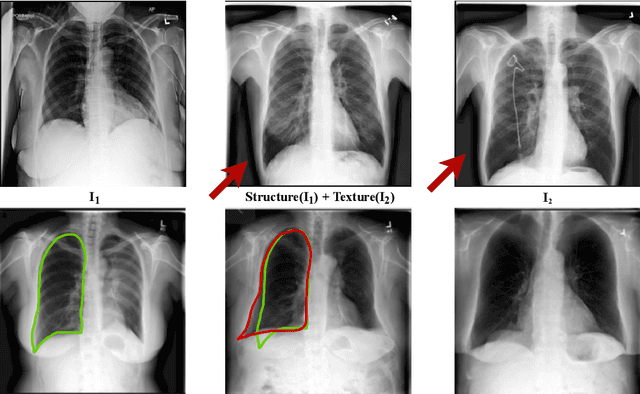

Well-labeled datasets of chest radiographs (CXRs) are difficult to acquire due to the high cost of annotation. Thus, it is desirable to learn a robust and transferable representation in an unsupervised manner to benefit tasks that lack labeled data. Unlike natural images, medical images have their own domain prior; e.g., we observe that many pulmonary diseases, such as the COVID-19, manifest as changes in the lung tissue texture rather than the anatomical structure. Therefore, we hypothesize that studying only the texture without the influence of structure variations would be advantageous for downstream prognostic and predictive modeling tasks. In this paper, we propose a generative framework, the Lung Swapping Autoencoder (LSAE), that learns factorized representations of a CXR to disentangle the texture factor from the structure factor. Specifically, by adversarial training, the LSAE is optimized to generate a hybrid image that preserves the lung shape in one image but inherits the lung texture of another. To demonstrate the effectiveness of the disentangled texture representation, we evaluate the texture encoder $Enc^t$ in LSAE on ChestX-ray14 (N=112,120), and our own multi-institutional COVID-19 outcome prediction dataset, COVOC (N=340 (Subset-1) + 53 (Subset-2)). On both datasets, we reach or surpass the state-of-the-art by finetuning $Enc^t$ in LSAE that is 77% smaller than a baseline Inception v3. Additionally, in semi-and-self supervised settings with a similar model budget, $Enc^t$ in LSAE is also competitive with the state-of-the-art MoCo. By "re-mixing" the texture and shape factors, we generate meaningful hybrid images that can augment the training set. This data augmentation method can further improve COVOC prediction performance. The improvement is consistent even when we directly evaluate the Subset-1 trained model on Subset-2 without any fine-tuning.